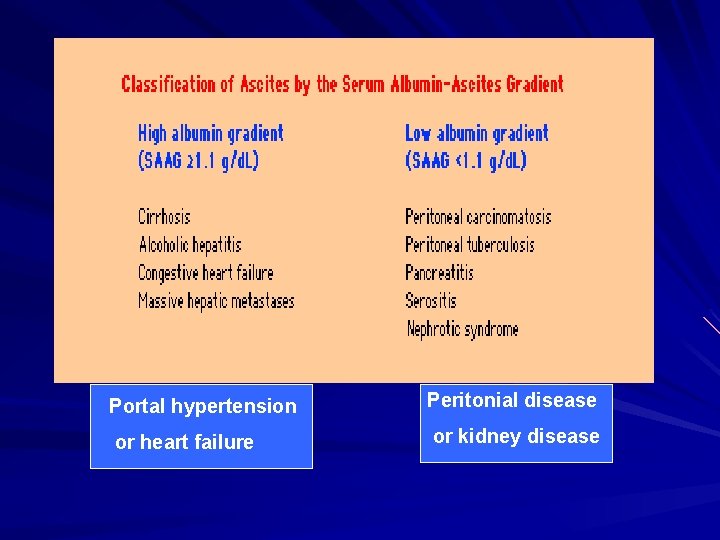

Portal hypertension Peritonial disease or heart failure or kidney disease